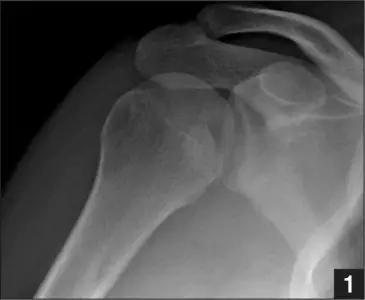

1. Hill-Sachs 损伤和反 Hill-Sachs 损伤

肩关节脱位时,肱骨头和关节盂发生撞击,肱骨头表面凹陷性骨折。

肩关节前脱位时发生的肱骨头后外侧凹陷性骨折,是经典的 Hill-Sachs 损伤(Hill-Sachs lesion);

而肩关节后脱位时发生的肱骨头前内侧凹陷性骨折,是反 Hill-Sachs 损伤(Reverse Hill-Sachs lesion/ McLaughlin lesion)。

Hill-Sachs 损伤的 X 片(来源:Hill-Sachs Injuries of the Shoulder)